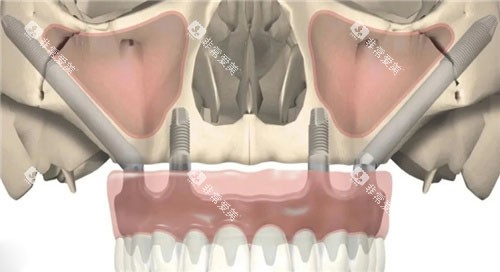

2.穿翼种植示意图

位置:种植体从上颌结节斜向后方,植入翼板骨的翼凹处。

手术步骤:

翻起上颌结节黏膜,暴露翼板骨区域。

使用导板引导钻针,在翼板骨上制备种植窝洞。

植入种植体,确保与翼板骨紧密结合。